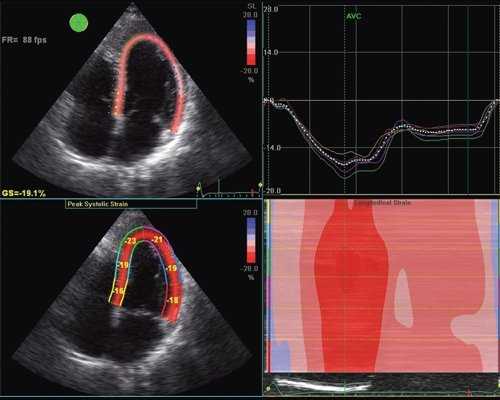

В настоящее время бурное развитие современных ультразвуковых технологий привело к появлению совершенно иных подходов к оценке функционального состояния сердца, которые на очень ранних этапах заболевания позволяют выявлять минимальные нарушения функции сердца. Мы еще не успели должным образом изучить возможности тканевой допплерографии, как появилась еще одна методика, получившая в англоязычной литературе название - speckle tracking. В отличие от тканевой допплерографии, основанной на эффекте допплера, speckle tracking основан на определении скорости движения миокарда при помощи отслеживания перемещения естественных акустических маркеров - пятнистых структур, на стандартном эхокардиографическом изображении в В-режиме (рис. 1).

Суть метода заключается в том, что акустические маркеры случайным образом равномерно распределяются по всему миокарду. Размер каждого пятна составляет от 20 до 40 пикселей (точек). Положение каждого пятна определяется и точно прослеживается на последовательных кадрах. Таким образом, можно определить расстояние, на которое перемещается пятно от кадра к кадру. Зная частоту смены кадров, можно определить скорость движения пятна. С целью повышения качества отслеживания пятнистых структур применяется высокая частота смены кадров - 60-100 кадров в секунду. Особенности движения сердца, вращение в грудной клетке, а также дыхательная экскурсия грудной клетки могут приводить к смещению пятен из плоскости сканирования. Однако эти изменения не успевают произойти в значимом количестве между двумя последовательными кадрами. Таким образом, по движению пятнистых структур можно получить данные о скорости, деформации и скорости деформации всех участков миокарда. Техника вычисления деформации по двухмерному изображению значительно проще, чем при использовании тканевой допплерографии, так как при этом отсутствуют ограничения, связанные с параллельностью движения объекта и ультразвукового луча. Для последующих вычислений достаточно одного сердечного цикла (рис. 2). Обработка ультразвуковых изображений проводится в режиме offline [2].

Рис. 2. Оценка продольной деформации левого желудочка с помощью ультразвуковой технологии speckle tracking в В-режиме.

С появлением ультразвуковой технологии speckle tracking стало возможным более детальное изучение регионарной систолической и диастолической функции не только продольных волокон, но и радиальных, окружностных, поскольку, новая технология лишена угловых ограничений, присущих тканевой допплерографии. Это делает возможным исследование продольной сократимости даже верхушечных сегментов левого желудочка. Благодаря технологии speckle tracking стало возможным изучение показателей апикальной и базальной ротации, скручивания и раскручивания сердца, что позволяет по-новому оценивать физиологию сокращения и расслабления миокарда.